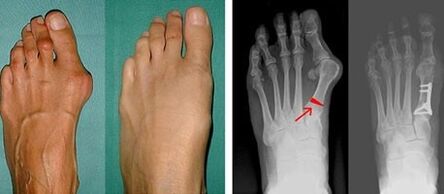

As the first step in identifying valgus of the big and little toe, the doctor conducts a visual examination.In this way, it determines the stage of development of the pathology.In order to identify detailed changes in the joints, x-rays and plantography are prescribed.

If the visual examination and x-rays yield no results, the patient is then referred to a plantography to determine possible flat feet.This method involves taking footprints, on the basis of which shoes or insoles with orthopedic properties are made for the patient.The patient is then prescribed podometry.This method uses computer analysis to determine the pressure of a person's weight on the feet.The results of advanced diagnostics form the basis for choosing a treatment method for curvature of the first and second toe.

The disadvantage of X-ray examination is the need to irradiate the patient's legs, which many patients do not like.They think it is too dangerous a method.In this regard, effective treatment of hallux valgus cannot be started without the results of plantography.